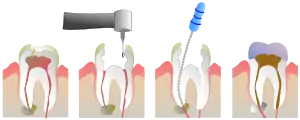

Наиболее частыми причинами повреждения или отмирания пульпы являются наличие трещины, либо глубокой кариозной полости в зубе[4]. В стоматологической практике в процессе эндодонтического лечения острого гнойного и хронического пульпита производится механическая и медикаментозная обработка системы корневых каналов зуба (депульпирование — удаление сосудов и нерва) с последующей пломбировкой (герметичной обтурацией) канала(ов). Данный вид лечения исполняется в двух вариантах:

- девитальная экстирпация — удаление сосудисто-нервного пучка проводится за 2 посещения. При первом создаётся сообщение с пульпарной камерой зуба, в которую накладывают девитализирующую пасту (так называемый «мышьяк», который уже практически не используется и заменён менее токсичной пастой на основе параформальдегида и анестетика).

- витальная экстирпация — при отсутствии выраженных воспалительных явлений, переходящих в периодонт, удаление сосудисто-нервного пучка и его обтурация проводится под анестезией в одно посещение. В канале оставляют лекарство (для антисептики и снятия воспаления). В процессе лечения необходимо сделать как минимум 2 рентгеновских снимка: первый — до начала лечения (для оценки длины и структуры каналов), а второй — после (для оценки качества пломбирования каналов).